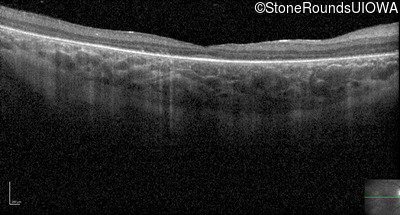

Optical Coherence Tomography - Right - 20/80 -1

Exemplar / OCT Stack